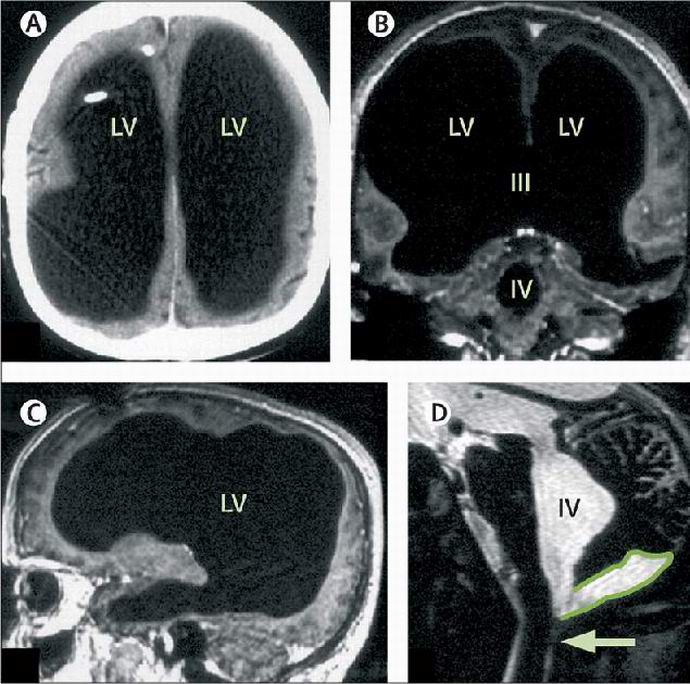

Když lékaři dosáhli Mathieuova mozkového skenování, ukázalo se, že jsou doslova šokován. Mozek muže byl tak malý že na obrázcích to nebylo prakticky patrné. Po sérii testy, lékaři zjistili, že mozkomíšní mok, cirkuluje u zdravého člověka v mozku a vylučuje se do oběhový systém, vyplnil lebku pacienta a odcházel velmi malé množství šedé hmoty. Udeřil to experti na hledání začali chápat povahu tohoto jevu a zjistili, že v dětství byl člověk léčen na hydrocefalus – jiný slovy, byl vyčerpán ze své mozkové nadbytečné tekutiny. K tomu lékaři Mathieu měl shunt a pak shunt odstranil. Ale, jak je vidět, problém poté nezmizel.

Po půl století se přebytečná tekutina nahromadila v hlavě Francouzův box a vytáhl jeho mozek. Úžasná, ale bolest v nohou se stal první a dosud jedinou komplikací spojenou s jeho nemoc. Za posledních osm let vědci pečlivě studovali tělo. Mathieu. Má se jednat o malé velikosti jeho mozku výsledkem hydrocefalu však bylo, jak muž žil tiše všechny ty roky jsou skutečným tajemstvím.